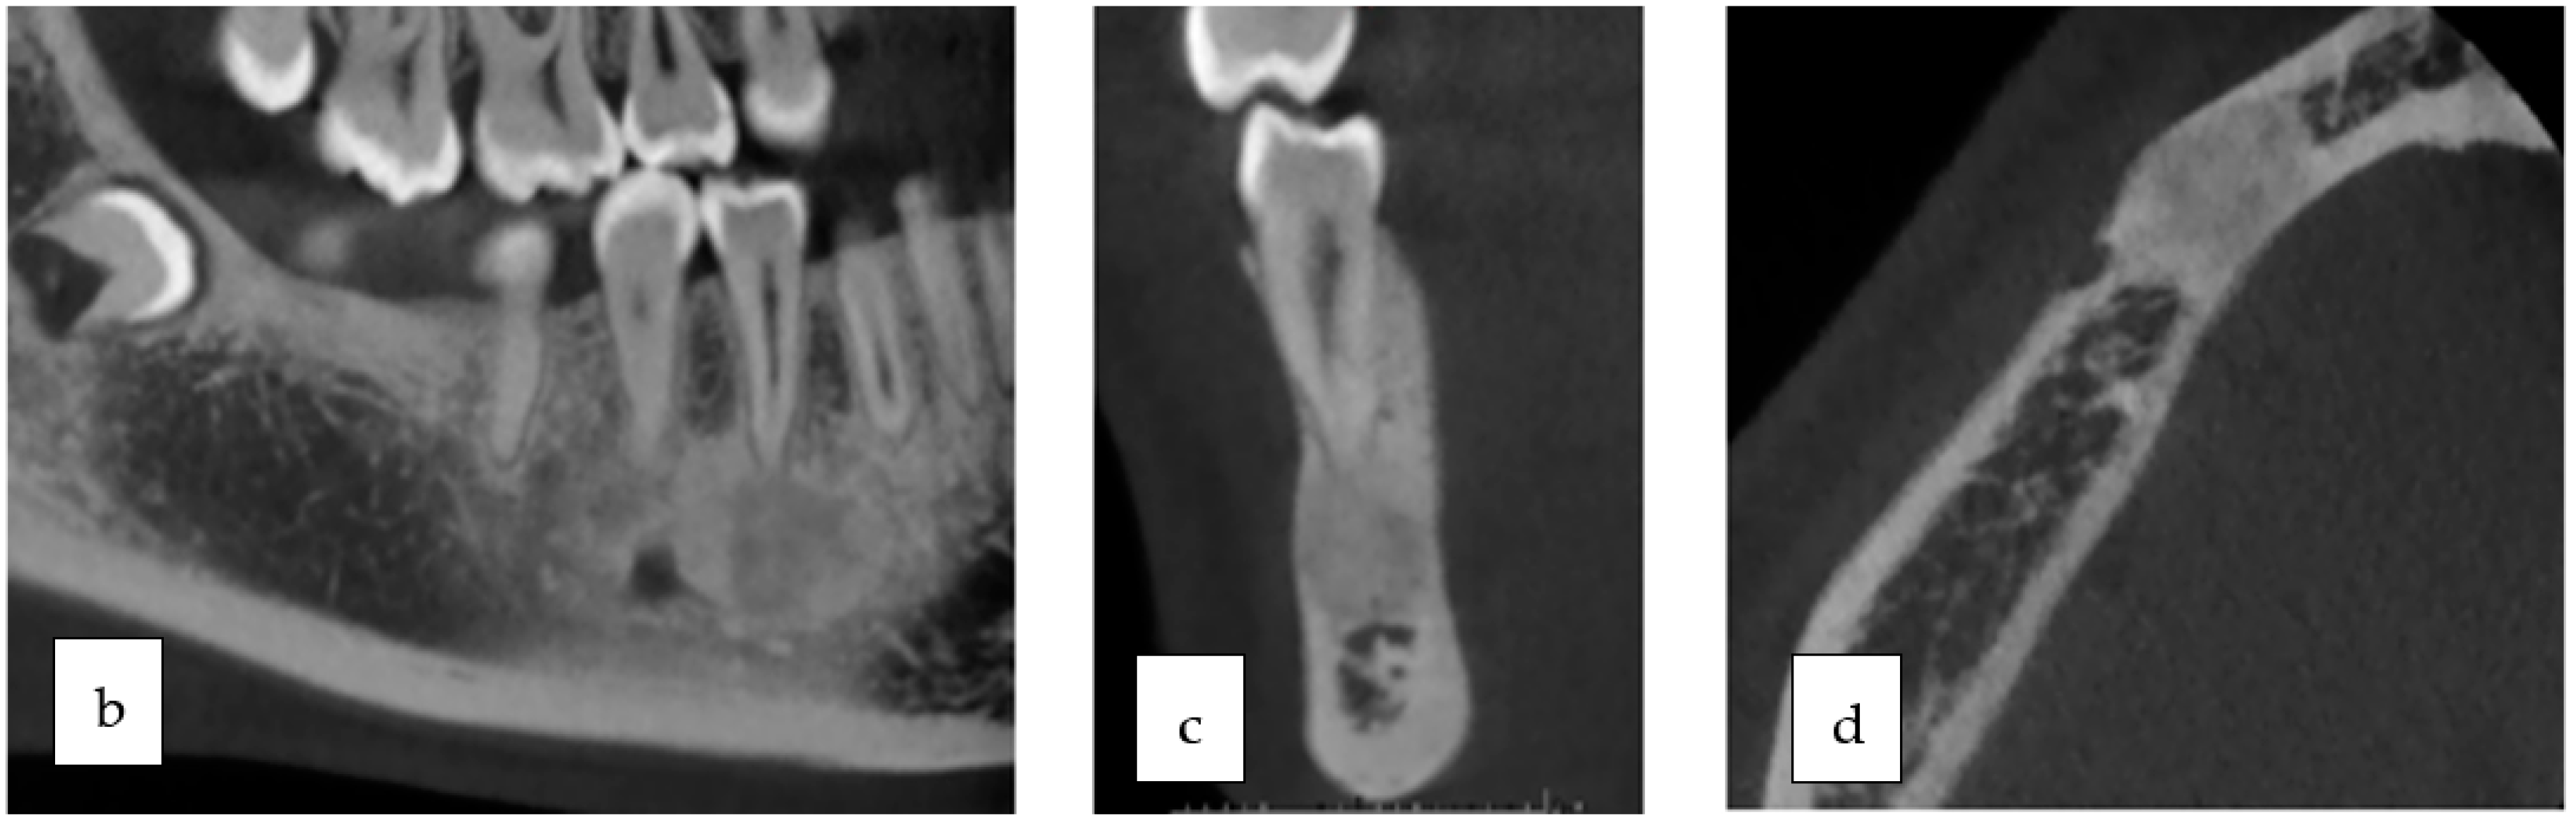

2. Case Presentation